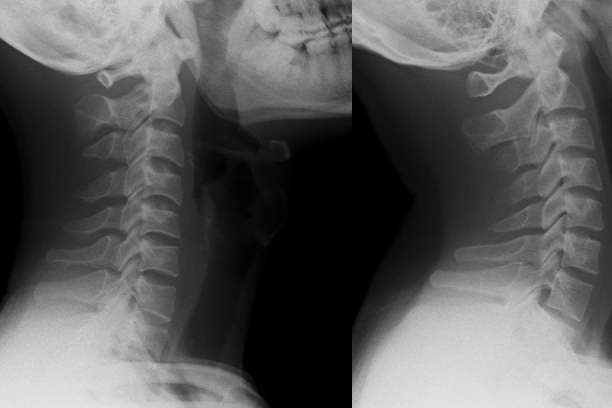

Các bác sĩ cho biết cổ của bệnh nhân yếu đến mức không thể tự nâng đầu lên. Phim chụp cho thấy phần cổ của anh biến dạng với khối phồng rõ rệt, do các đốt sống bị kéo giãn bất thường trong thời gian dài.

Các kết quả chụp chiếu ghi nhận đốt sống cổ của bệnh nhân bị biến dạng, trật khớp và hình thành mô sẹo. Ban đầu, các bác sĩ sử dụng nẹp cổ để hỗ trợ nâng đầu nhưng người bệnh bị tê khi đeo nên không thể tiếp tục áp dụng phương pháp này.